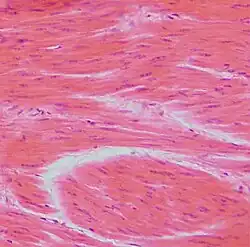

Histologischer Schnitt glatter Muskulatur (HE)

Es gibt eine Unzahl verschiedener histologischer Färbungen, die im Laufe der letzten 120 Jahre entwickelt wurden. Der Großteil stammt aus den ersten 30 Jahren des vorigen Jahrhunderts. Im modernen Histolabor hat sich eine überschaubare Anzahl an Färbungen durchgesetzt. An erster Stelle steht die Hämatoxylin-Eosin-Färbung (HE-Färbung) als Routine- und Übersichtsfärbung. Dafür werden meist computergesteuerte Färbeautomaten eingesetzt. Daneben werden für bestimmte Fragestellungen sogenannte Spezialfärbungen (meist von Hand) durchgeführt.